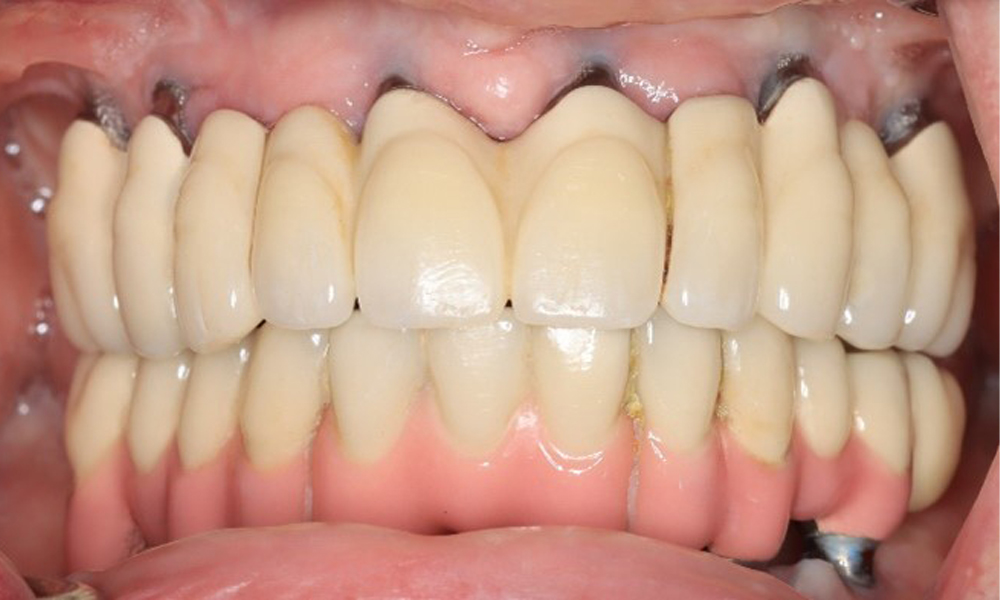

A 74-year-old patient presents for a consultation. The anamnesis shows that the patient has well-controlled hypertension and is taking Lixiana. Additionally, the patient had a kidney carcinoma in 2020. The patient’s lifestyle is unremarkable. She has no natural teeth left and has six implants in both the upper and lower jaws, which are fitted with crowns or bridges. Current findings show no peri-implant mucositis or peri-implantitis; however, there are occasional minor bleeding at the implant sites.

Provisions: Implants in regions 011, 013, 015, 021, 023, 025, 031, 033, 035, 042, 044, 046

When instrumenting implants, a special approach is required. Choosing appropriate powders and instruments is crucial for preserving the implant surface while ensuring effective cleaning. This includes the targeted use of powder jet devices with specialized perio-tips. The choice of the right powder can be adjusted based on needs and risks, such as considering abrasive levels and dietary requirements (e.g., sugar-free, low-salt).

The peri-implant situation is currently stable. Due to the complexity of the superstructures, the patient has a moderate risk of development and a low risk of progression for peri-implant diseases.